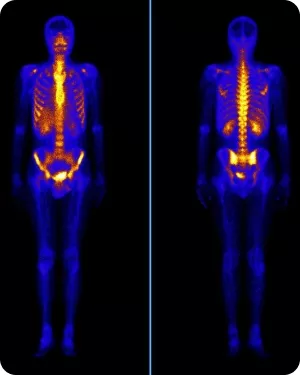

Остеосцинтиграфия

Остеосцинтиграфия с радиофармпрепаратом (РФП) на основе изотопа технеция (99mТс) является скрининговым методом выявления метастазов в костях скелета при большинстве злокачественных опухолей, способных метастазировать в кости.

Это обусловлено возможностью относительно быстрого одномоментного исследования всего скелета, высокой устойчивостью РФП к возможным у пациента металлическим имплантантам без формирования артефактов. Радиоактивный изотоп технеция (99mТс) активно накапливается в участках костей с повышенной остеобластической активностью, но слабо чувствителен к остеолитическим и смешанным метастазам.

Чувствительность остеосцинтиграфии находится диапазоне от 86% до 92%, а специфичность – в диапазоне от 57% до 95%. Очаги гиперфиксации технеция 99mТс требуют обязательного подтверждения рентгенографией, МРТ (при подозрении на поражение мозга), КТ или ПЭТ/КТ.

• Если по данным остеосцинтиграфии выявлен единичный очаг накопления РФП, то достаточно его подтверждение/исключение проведением КТ без контраста этой зоны скелета

• Если по данным остеосцинтиграфии выявлены множественные очаги накопления РФП, то методом уточняющей диагностики может являться ПЭТ/КТ с тропным к основной опухоли РФП

Остеосцинтиграфия для оценки эффективности противоопухолевого лечения в комбинации с остеомодифицирующими агентами, как правило, не рекомендуется.